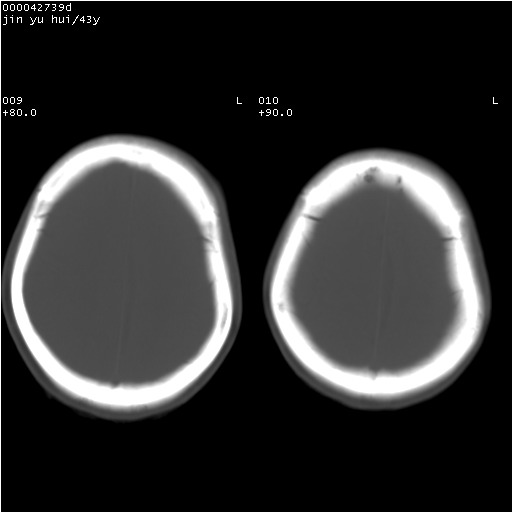

患者 女,43岁。头部外伤26天,经住院治疗,现头痛减轻。申请ct复查,了解颅内情况。

临床诊断:2级脑外伤。

颅脑ct轴位平扫(层厚、层距均为10mm),图像如下:

纵裂旁硬膜下水瘤,左额部头皮肿胀

大脑镰左旁慢性硬膜下血肿.左额部头皮血肿.